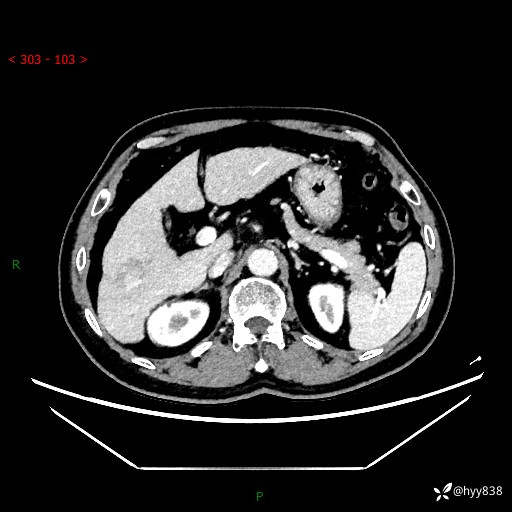

肝脏CT平扫